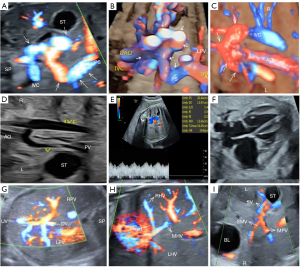

Case 1: A 34-year-old pregnant woman at 33 weeks and 1 day of gestation showed the following specific sonographic features: An anomalous vessel originating from the PV sinus before splitting into the left and right branches. This vessel traveled behind the gastric bubble, crossed over the abdominal aorta, and drained into the IVC (Figure 2A-2C). The IVC was dilated, measuring about 0.41 cm in width (Figure 2D), and the anomalous vessel exhibited a portal venous flow pattern with a peak systolic velocity (PSV) of 20.4 cm/s (Figure 2E). The fetal heart was observed to be mildly enlarged (Figure 2F), and the IHPVS and hepatic venous system, including their tributaries, were clearly delineated (Figure 2G,2H), along with the MPV, SV, and SMV (Figure 2I). Serial ultrasound assessments of the shunt vessel and cardiac function were conducted until the neonate’s delivery at 36 weeks and 6 days of gestation.

The 6-month postnatal follow-up revealed that the shunt vessel was still present, along with abnormal liver function tests showing increased alanine aminotransferase (ALT) and aspartate aminotransferase (AST) levels, as well as hypoproteinemia. The infant subsequently underwent percutaneous shunt treatment at another medical facility. An indirect venography performed through the SMV showed the abnormal shunt from the PV to the IVC (Figure 3A). A vascular occluder was deployed at the site of the shunt to successfully embolize the vessel (Figure 3B). Subsequent indirect venography performed through the SMV confirmed the absence of portal-to-IVC shunting (Figure 3C). The child’s postnatal prognosis at 1 year and 6 months was favorable.

Type B: PV draining into renal vein

Case 3: A 35-year-old expectant mother at 32 weeks and 3 days of gestation underwent an ultrasound that revealed an anomalous vessel emerging from the proximal portion of the PV. This vessel extended posteriorly and to the left, then looped back, descended, and ultimately emptied into the left renal vein (LRV) (Figure 4A-4C). The fetal heart was observed to be mildly dilated (Figure 4D), and the DV, the main stem of the PV, and its intrahepatic branches were all visualized. Surveillance of the shunt vessel and cardiac function via ultrasound was maintained until the neonate’s delivery at 35 weeks and 6 days.

Postnatal ultrasound confirmed the shunt vessel’s drainage into the LRV (Figure 4E). After birth Postnatal three-dimensional CT angiography demonstrated two anomalous vessels originating from the main trunk of the PV: a large shunt vessel (v1, marked by a red arrow in Figure 4F) draining into the LRV, and a smaller shunt vessel (v2, indicated by a white arrow in Figure 4F) draining into the SMV. During the 6-month postnatal follow-up, the shunt vessels persisted. Additionally, the liver function tests showed abnormalities (elevated ALT and AST levels), and the cardiac enzyme panel indicated increased levels of creatine kinase, creatine kinase-myoglobin, and myoglobin. The child underwent ligation of the shunt vessel (v1) at another medical facility and was diagnosed with CEPS, specifically Abernethy type II. The prenatal diagnosis was consistent with the surgical outcome, and the child experienced no complications postoperatively. The child’s postnatal prognosis at the 4-year, 2-month follow-up was favorable.